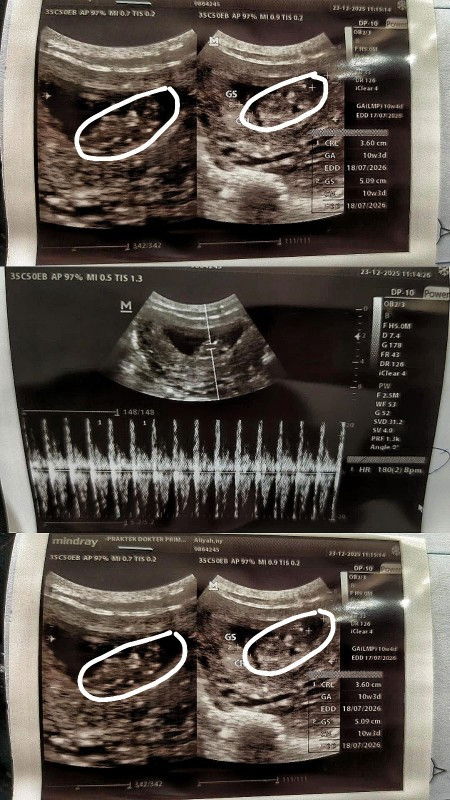

Ada yang sama gak bun hamil 10minggu hasil USG belum kelihatan

alhamdulillah saya USG 10 minggu udh keliatan bun, detaknya juga udh tinggi garisnya udh kuat alhamdulillah.coba pindah dokter, atau USG Trans vaginal. kalau gak, gpp nunggu sampai 13 minggu sambil kencengin asam folat, kalsium, sama vitamin D nya

aku bun 10 weeks lebih pas USG di puskesmas keliatan kantongnya aja 🥲 padahal pas 7 weeks udah ke obgyn USG transvaginal sih udah ada janin + djj

tapi saya kemarin dipukesmas ada bayinya Bun sesuai ukuran umur 10w